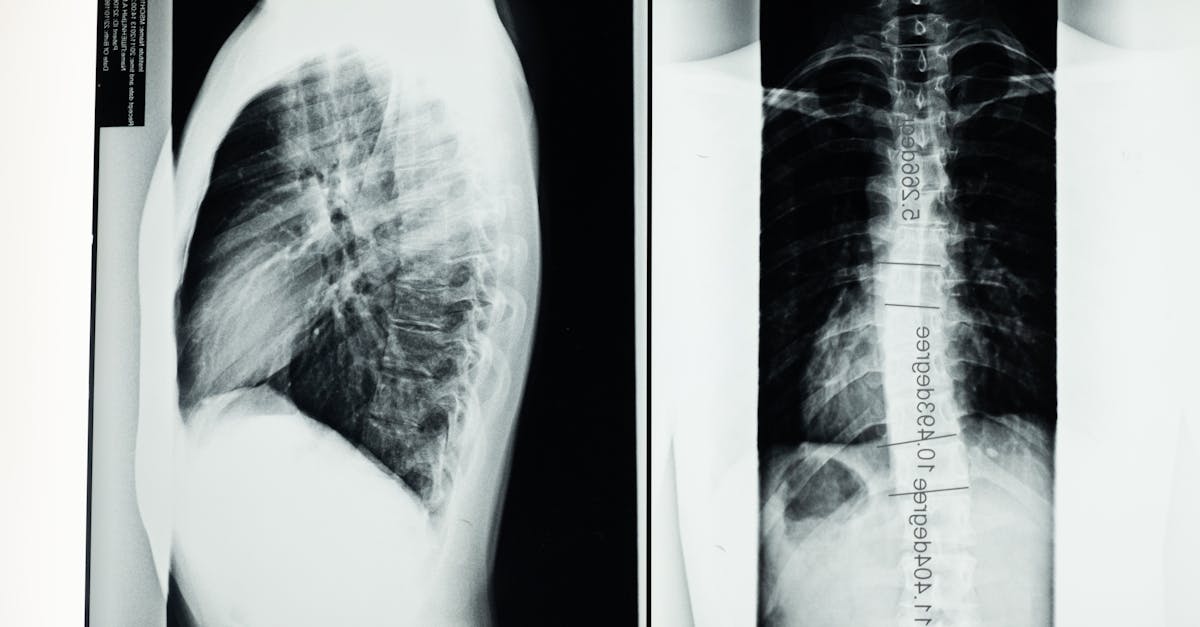

La décompression neurovertébrale est une approche thérapeutique qui vise à réduire la pression exercée sur les structures vertébrales. En créant un espace entre les vertèbres, cette technique favorise un meilleur alignement de la colonne et permet une meilleure circulation sanguine, ce qui contribue à la régénération des tissus. Son objectif principal est d’atténuer les douleurs liées à des affections telles que les hernies discales ou la sténose spinale, tout en améliorant la souplesse générale de la colonne vertébrale.

La méthode de décompression neurovertébrale se base sur le principe fondamental que des vertèbres correctement alignées favorisent une meilleure mobilité articulaire. En relâchant les tensions sur les nerfs et les disques, elle permet d’atténuer les douleurs associées à des affections telles que les hernies discales ou la sténose spinale. Ce traitement est d’autant plus pertinent dans le contexte actuel où de nombreuses personnes font face à des problèmes de mobilité dus à un mode de vie sédentaire ou à des lésions répétées.